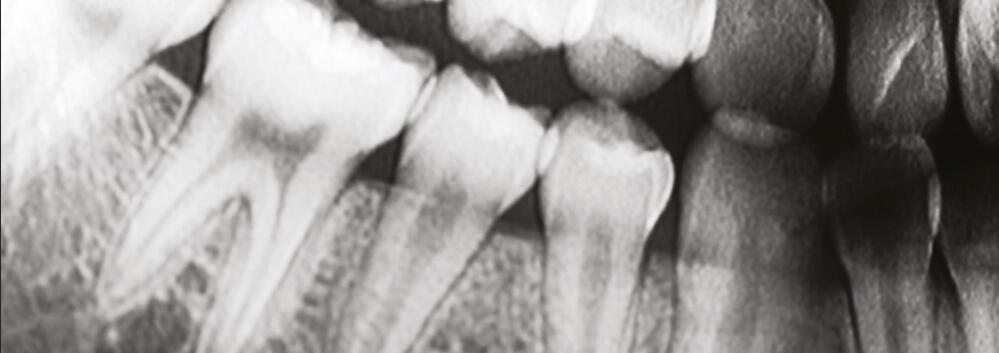

4. **圖像質量**:使用碘化銫作為閃爍材料的X射線平板探測器能夠提供高分辨率和高對比度的圖像。這對于醫學成像尤其重要,因為它可以幫助醫生更準確地診斷和評估疾病。

針狀碘化銫閃爍體的掃描電鏡圖像:針狀晶體具有限光作用,能夠有效降低光的散射,進一步提高空間分辨率